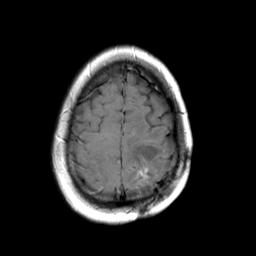

MR Study #3 -- Slice #43